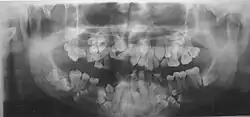

• The permanent teeth include supernumerary teeth. Unless these supernumeraries are removed they will crowd the adult teeth in what already may be an underdeveloped jaw. If so, the supernumeraries will probably need to be removed to make space for the adult teeth. Up to 13 supernumerary teeth have been observed. Teeth may also be displaced. Cementum formation may be deficient.[13]

• Failure of eruption of permanent teeth.

Different features of the dysostosis are significant. Radiological imaging helps confirm the diagnosis. During gestation (pregnancy), clavicular size can be calculated using available nomograms. Wormian bones can sometimes be observed in the skull.[20]